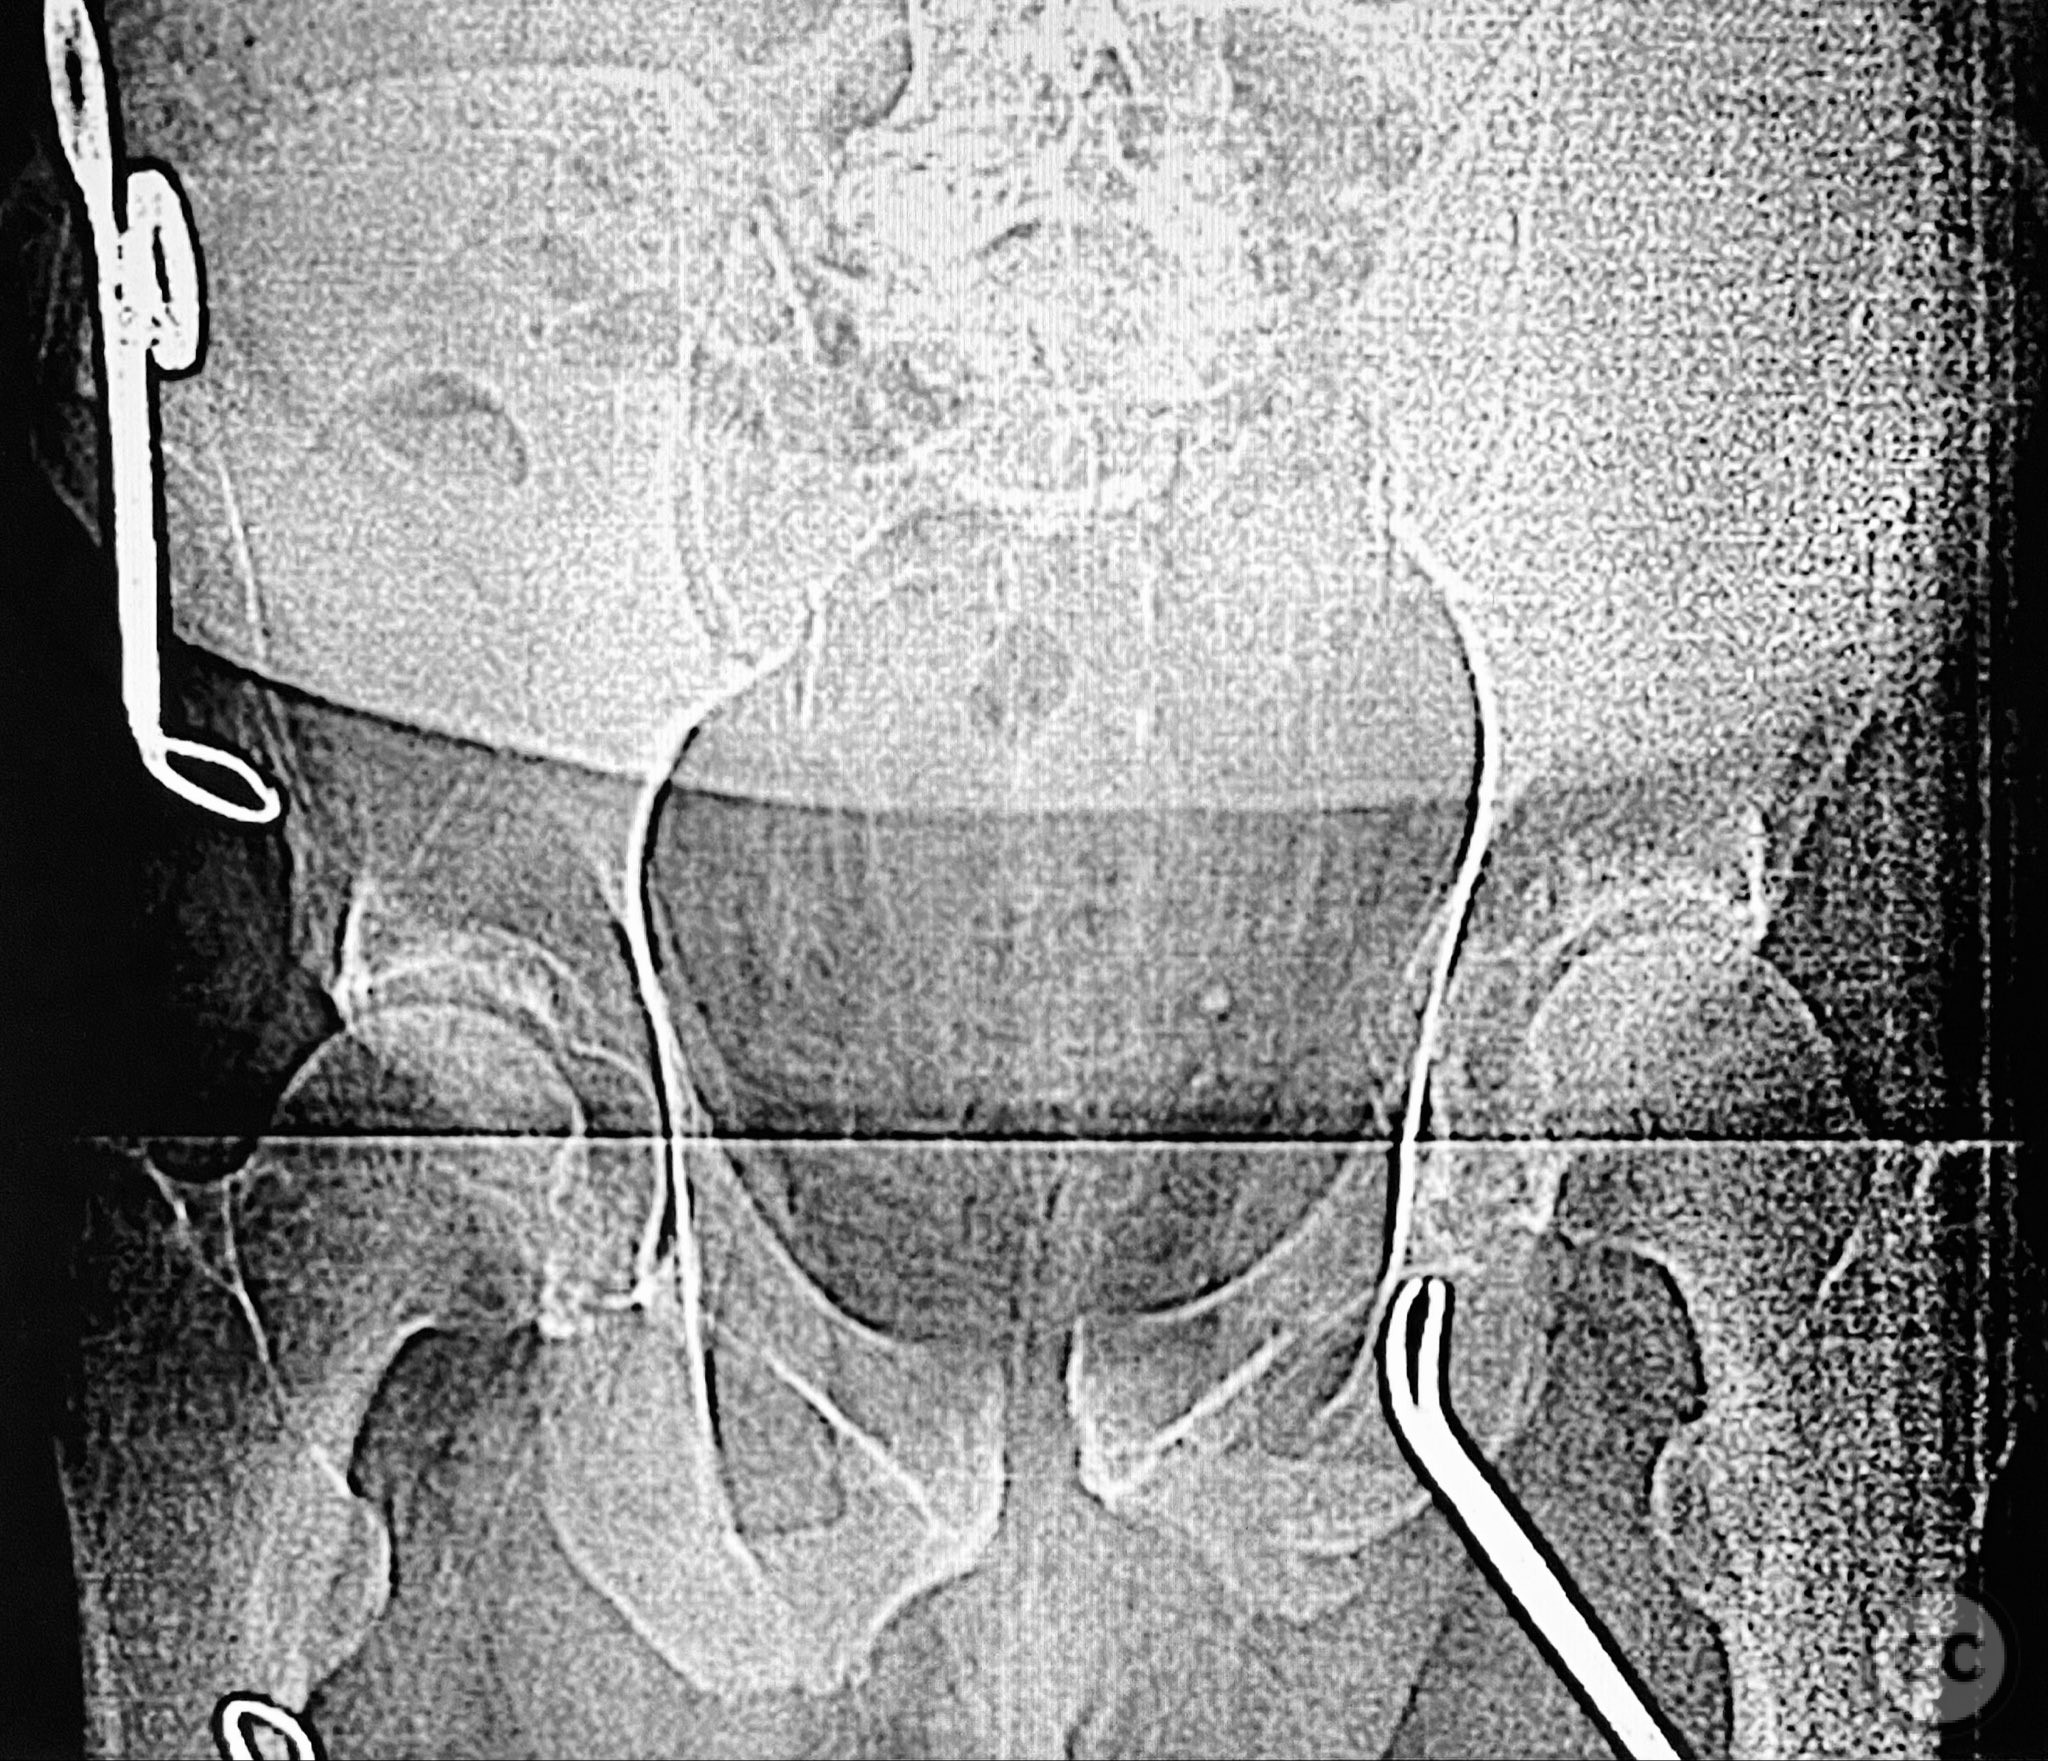

Planning remarks:  The preoperative plan included staged open reduction and internal fixation of the posterior pelvic ring via a dorsal approach in the prone position, utilizing direct visualization and reduction of the sacral fracture, followed by iliosacral and transiliac screw fixation. Definitive management of the anterior ring (symphysis pubis and ramus) was planned subsequently via an anterior approach in the supine position for reduction and stabilization.

Anatomical surgical approach:  The posterior approach involved a midline longitudinal incision over the sacrum, subperiosteal dissection to expose the dorsal sacral cortex, and direct assessment of fracture reduction using the cortical edges as reference points. Reduction was achieved and maintained with clamps. Iliosacral screws were inserted percutaneously under fluoroscopic guidance, supplemented by a posterior transiliac screw traversing from one ilium to the contralateral ilium across S1/S2. The anterior approach utilized a Pfannenstiel incision for exposure of the symphysis pubis and adjacent rami; reduction was achieved with pointed reduction forceps and stabilized with a symphyseal plate and additional ramus screws as indicated.

The posterior reduction was facilitated by direct visualization of the dorsal sacral cortex, allowing precise assessment and clamping of the comminuted fragments prior to screw fixation. The iliosacral screws were placed without cannulated instrumentation longer than 130mm, reflecting historical implant limitations at the time of surgery. Postoperative CT confirmed satisfactory reduction and fixation of the posterior ring, though suboptimal positioning of iliosacral screws was noted (contained within the osseous fixation pathway but not optimized for maximal safety or precision). The anterior ring was subsequently addressed in a staged fashion, with anatomical reduction and stable fixation achieved via open technique. This case highlights technical challenges in achieving optimal screw trajectory and length, particularly with historical implant constraints, as well as the importance of staged management in complex pelvic ring disruptions.